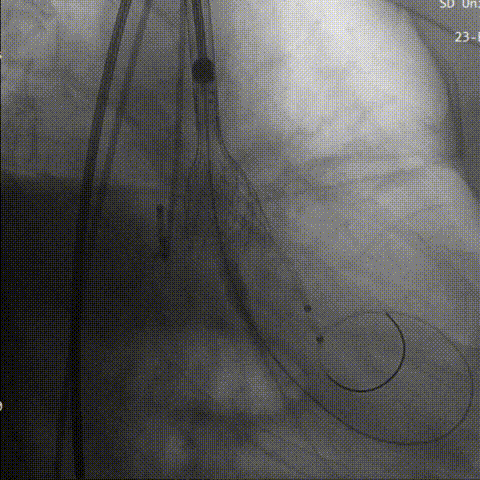

初始定位

术者结合DSA影像,多角度观察瓣膜情况,在瓣膜达到一个稳定位置后,缓慢释放到工作位,造影评估显示反流明显,行第一次回收。

工作位评估

第一次回收

第二次定位

释放到工作

造影评估下瓣环上2mm定位,缓慢释放,瓣膜下滑到瓣环平面水平,瓣膜位置良好,继续释放到工作位进行评估,反流较为显著。决定再次回收。

回收后第三次进行瓣上2mm定位,确定释放位置稳定后没缓慢是放到工作位,猪尾导管造影显示无反流。

第三次定位

最后三分之一瓣膜稳定脱钩,造影显示,无明显瓣周漏及反流,瓣膜形态佳,工作稳定。

瓣膜完全释放

猪尾造影评估